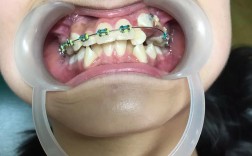

牙齿矫正金属矫正器,作为临床应用最广泛、历史最悠久的正畸装置,通过机械性外力引导牙齿移动至理想位置,是解决各类错颌畸形的重要手段,其核心结构由托槽、弓丝、结扎丝或橡皮圈组成,其中托槽通常由不锈钢或钛合金制成,通过专用粘接剂固定于牙齿唇颊面,...